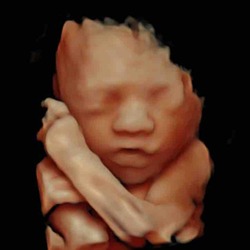

Daar zie je precies een piemeltje en een balletje, is mijn echo, weet ook nog niet 100% zeker maar dat maken ze mij wijs Hahaha 😅🙈

Staat inderdaad ook omhoog, dus een jongen!

Echt overduidelijk een jongen hoor haha! Onwijs leukkk❤️😍